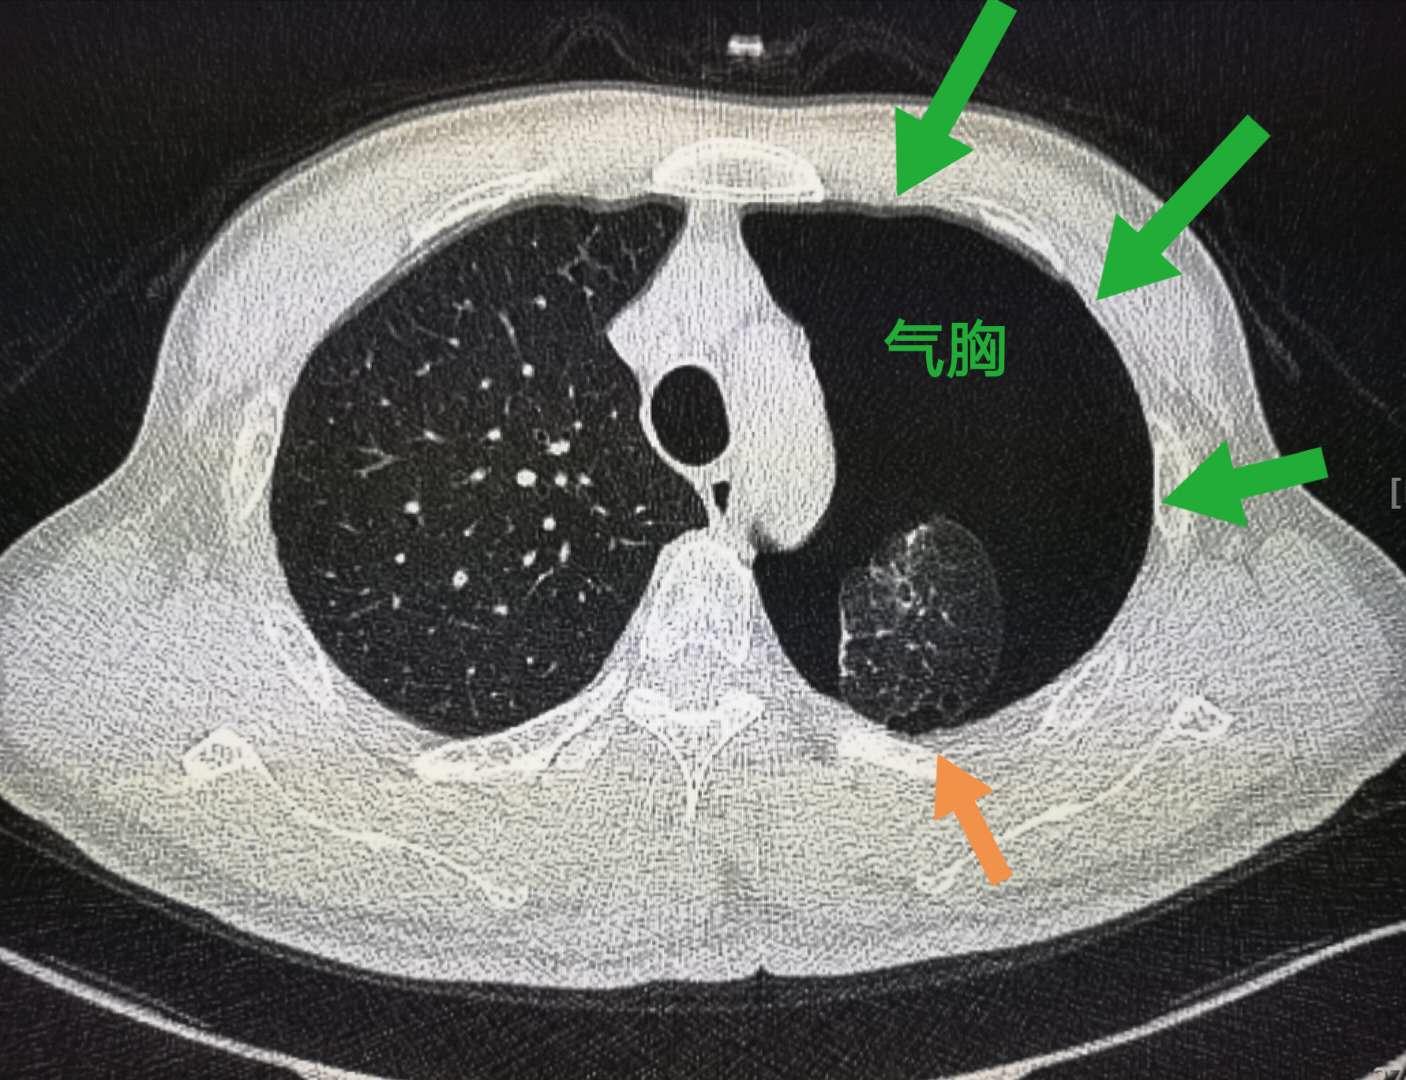

像上图这个小伙子就相对幸运一点,肺尖部胸膜下的肺大泡(橙色箭头)破裂,引起自发性气胸,没有伴发出血,经导管引流后顺利出院了。

最后简单解说一下自发性气胸

原发性自发性气胸是指无明确肺部疾病,在无诱发事件的情况下发生的气胸。常见原因就是上面这个病例,是由胸膜下肺大泡破裂所致。